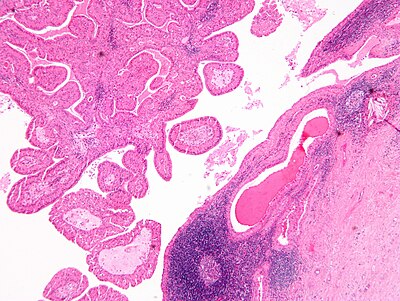

2

Diagnosis?

Papillary cystadenoma lymphomatosum2.jpg

Acinic cell carcinoma

Adenoid cystic carcinoma

Basal cell adenocarcinoma

Basal cell adenoma

Carcinoma ex pleomorphic adenoma

Chronic sialadenitis

Cribriform adenocarcinoma of the minor salivary gland

Epithelial-myoepithelial carcinoma

Hyalinizing clear cell carcinoma

Mucoepidermoid carcinoma

Mammary analogue secretory carcinoma

Oncocytoma of the salivary gland

Pleomorphic adenoma

Polymorphous low grade adenocarcinoma

Salivary duct carcinoma

Sebaceous lymphadenoma

Warthin tumour